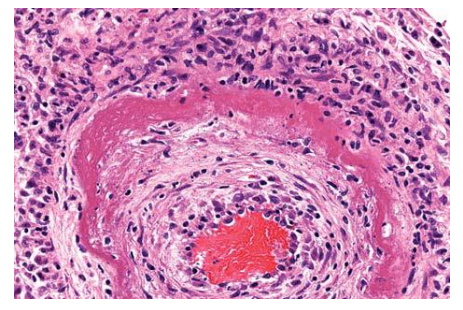

Fat Necrosis

Fibrinoid necrosis